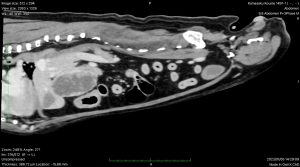

術前検査において、CTを撮影し肝臓の尾状葉に腫瘤が局在することを確認している